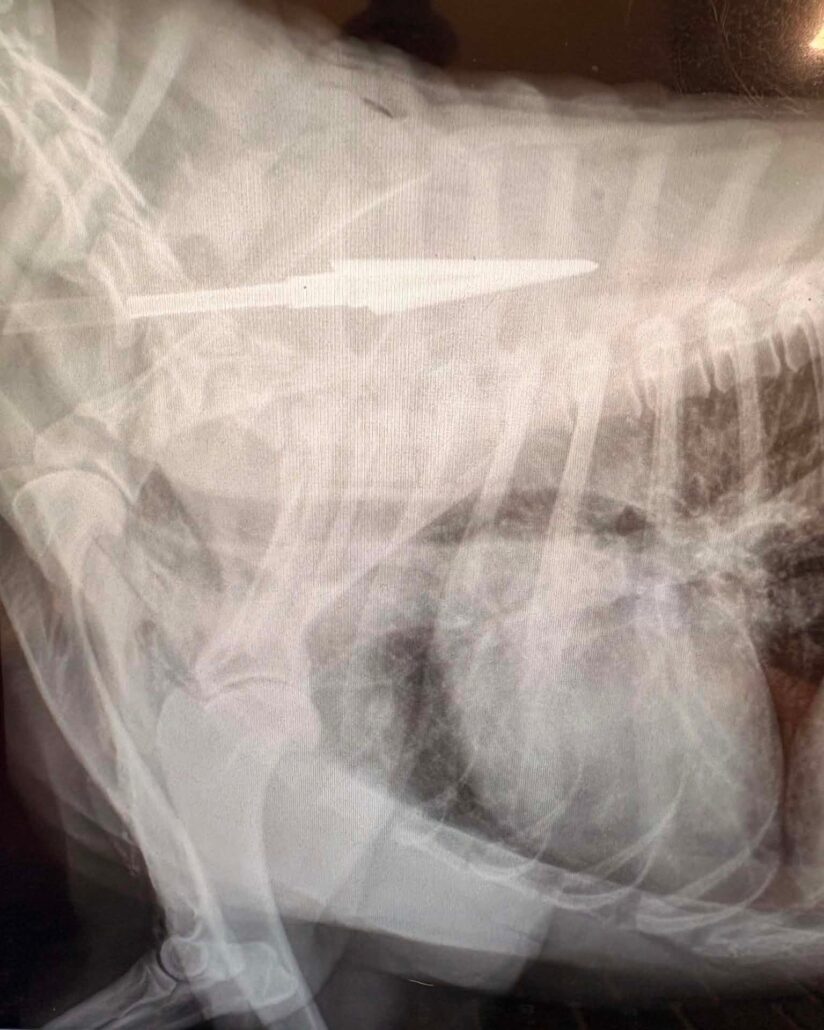

And NOW, almost a year later, another dog arrived at Stray Rescue of St Louis with an arrow deeply embedded in his shoulder. Luckily, the arrow had not hit any vital organs.

Meet Shy Guy, and when he arrived at the rescue organization just a few days ago, he was rushed to surgery.

Shy Guy had been in excruciating pain, and fortunately his surgery was also a success. Compared to how he felt when he arrived, and even though his shoulder is very sore while his muscles and stitches heal, he is making forward progress.